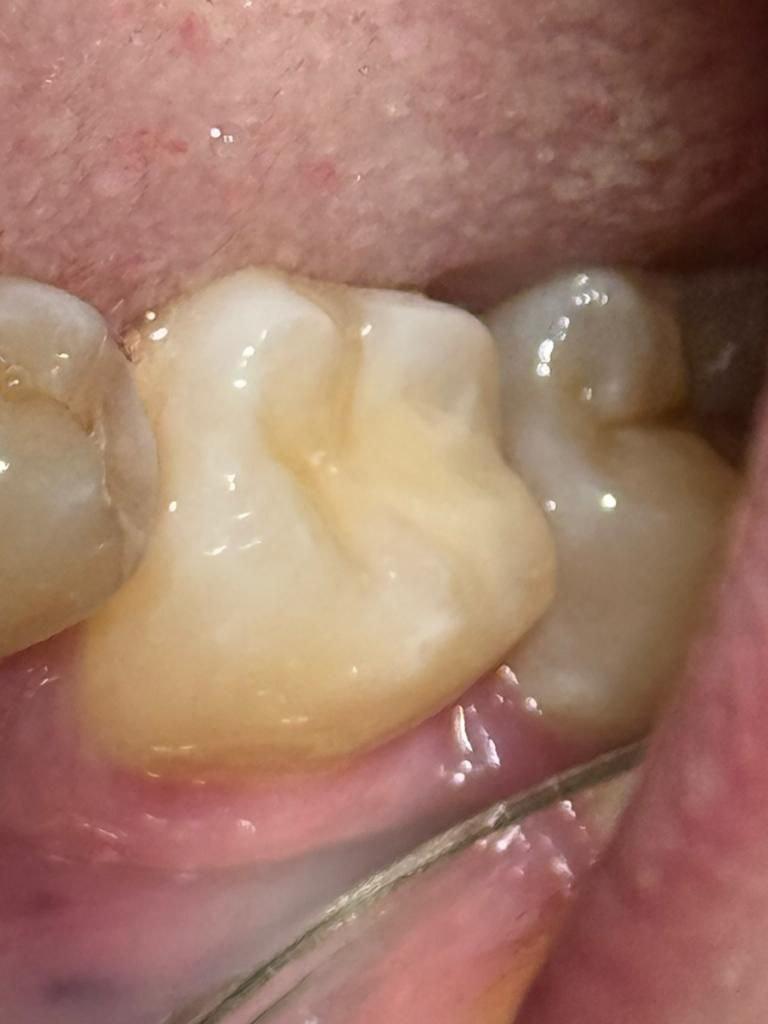

Эстетика жевательного зуба

На фото «До» — моляр, который казался просто рабочим зубом. Но при ближайшем рассмотрении: чёрные точки на жевательной поверхности, на щечной стенке. Всё то, что не болит, но портит ощущение чистоты.

Я убрал старые пломбы, убрал пигментацию, убрал каждый тёмный миллиметр. Прошёлся по трём поверхностям: окклюзионной (жуём), щечной (видна при улыбке) и дистальной (контакт с соседом). Восстановил анатомию послойно, материалом Filtek Z550, с вниманием к каждому бугру.

На фото «После» — ни одной чёрной точки. Зуб выглядит так, будто его никогда не касался кариес. Чисто, свежо, анатомично.

Я за то, чтобы даже дальние зубы были красивыми. Потому что чистота не терпит исключений.